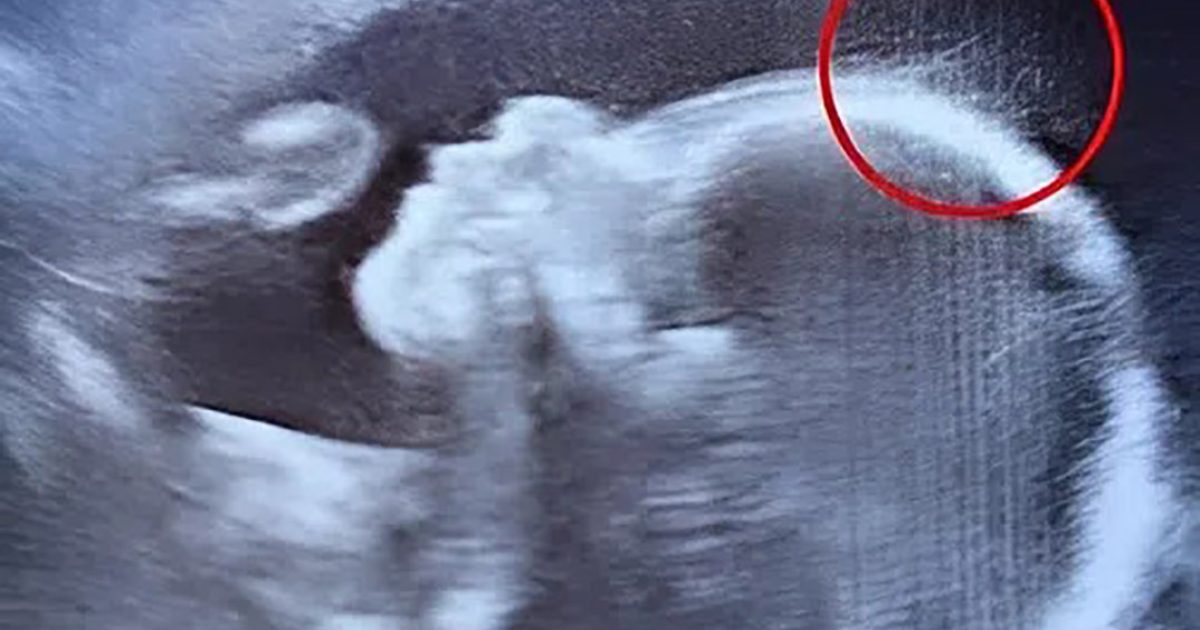

28 novembre 2025 Les médecins retirent l’assistance respiratoire tandis que la famille fait ses adieux au nouveau-né… mais soudain, il se met à respirer